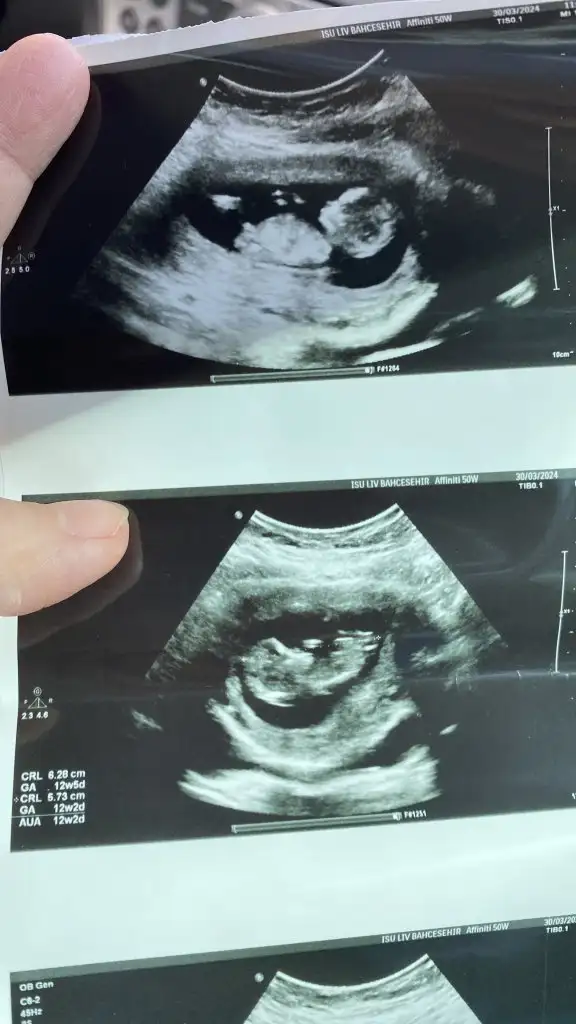

Kızlar biz de ikili taramadan çıktık şimdi

Ense 1.4 iyi dedi. Burun kemiği oluşmuş. Ultrasonda herhangi bir sorun yok dedi 🥰

12+2 diye gittik 13+0 çıktı yavrum:nazar:

Eller ayaklar kıpırdıyor 🥹 benim gözler hep dolu dolu 🙃

Cinsiyet tahmininde bulunabilirim ama kesin diyemem isterseniz sonraki kontrolü bekleyelim sürprizi kaçmasın dedi

Biz de kesin olsun dedik söylemedi :nazar:

Fotimizi ekliyorum 🥰